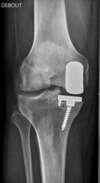

arthrose interne du genou sans déformation osseuse du squelette : traitement chirurgical par pose de prothèse partielle (Prothèse Unicompartimentaire Interne)